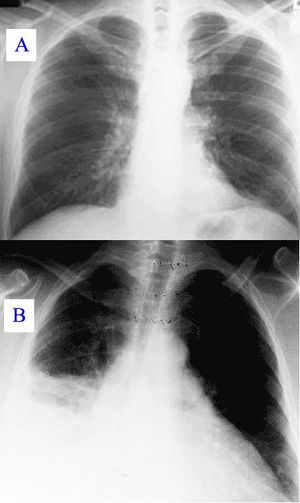

Pneumonia as seen on chest x-ray. A: Normal chest x-ray. B: Abnormal chest x-ray with shadowing from pneumonia in the right lung (white area, left side of image).